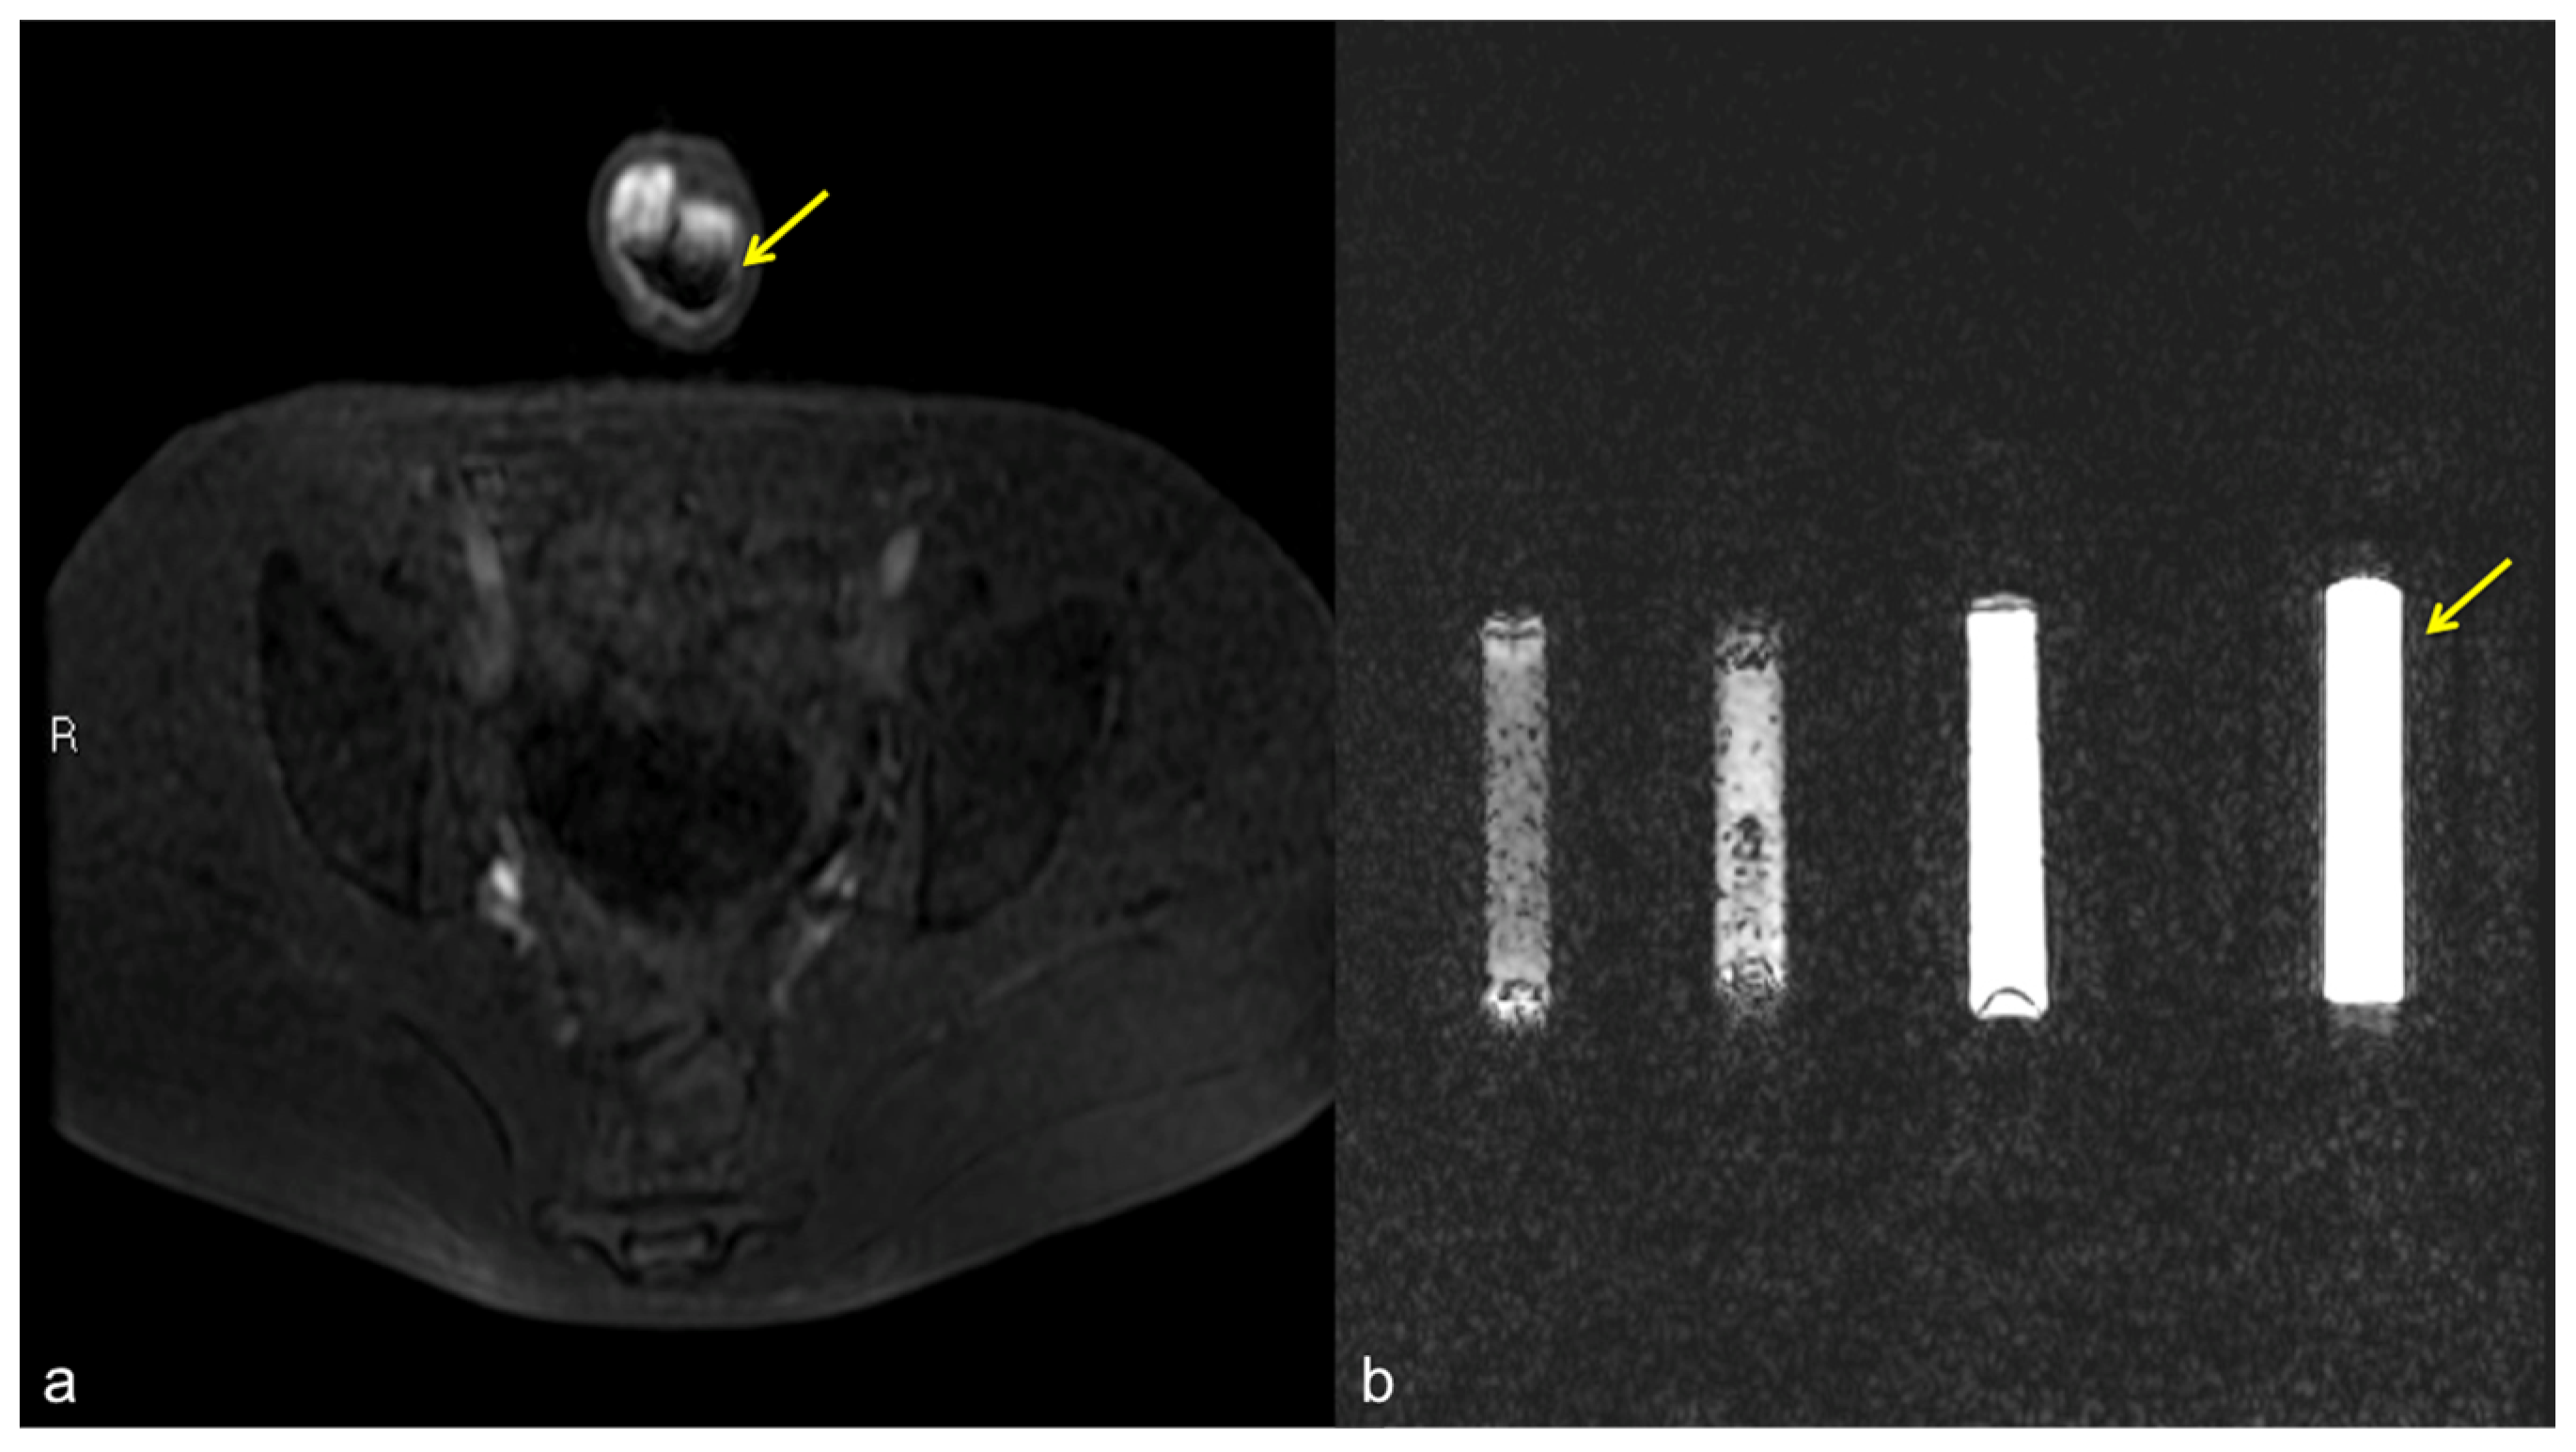

Figure 11.

Pseudo-stratification effect of the contrast agent. Cav-RM GRET1W 3D fat sat axial sequence after intra-cavernous administration of contrast agent (a): pseudo-layering artifact of the contrast agent in the cavernous bodies (arrow). Saline dilution of the contrast agent in a test tube (b): from the left side of the figure, note the progressive optimization of the contrast agent signal from 5 cc, 3 cc, 2 cc, to the optimal ratio of 1 cc of contrast agent in a total volume of 20 cc of solution (contrast agent + saline) (arrow).